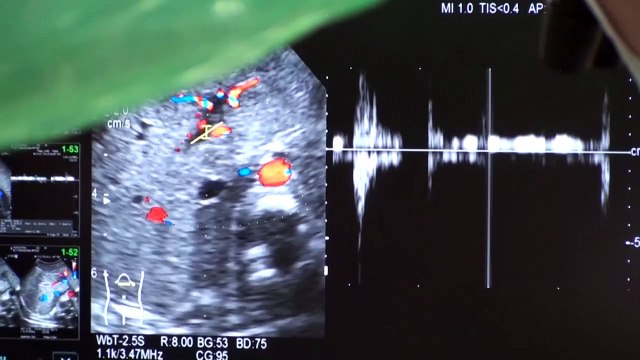

celulasmadreenmexico.com Entrevista con el Dr. Hector Fabian Nario Alvarez en su clinica de celulas madre. Tu salud al alcance de tus manos!